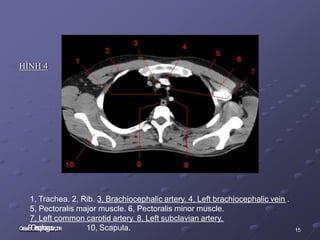

HÌNH 4

1, Trachea. 2, Rib. 3, Brachiocephalic artery. 4, Left brachiocephalic vein .

5, Pectoralis major muscle. 6, Pectoralis minor muscle.

7, Left common carotid artery. 8, Left subclavian artery,

4 10, Scapula. 15